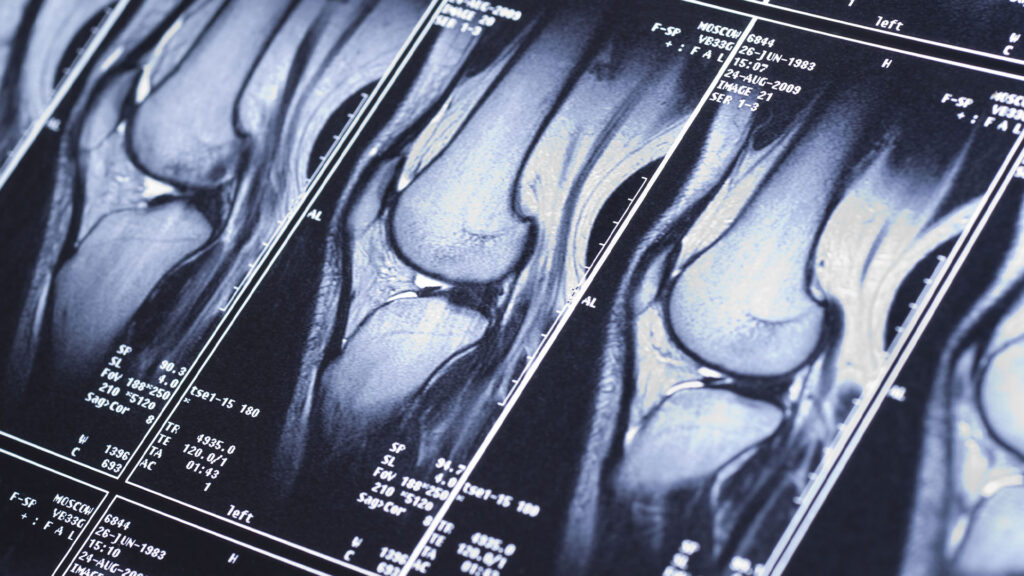

MRI Sugar Land Hospitals March 3, 2024 by Ali Mustafa MRI Sugar Land Hospitals About Ali Mustafa Previous Post:What an MRI Can Tell You After a Sports Injury